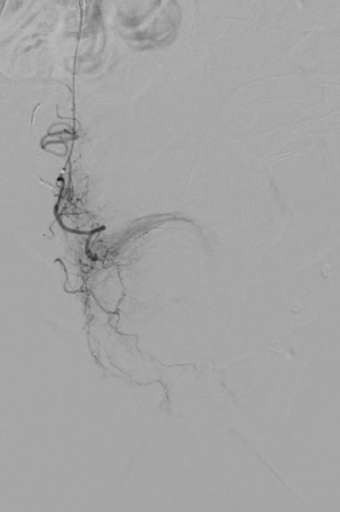

תמונות מהצנתור:

- ממשיכים כעת לצד ימין וניתן לראות שהעורקים נצבעים בהיקף הערמונית בלבד מכיוון שהרקמה נחסמה כבר מקודם דרך הצד השני.

- לצורך חסימת העורקים הראשיים הוזרק נוזל הממלא את חלל העורק וחוסם אותו. צבעו של החומר שחור בדומה לחומר הניגוד.

- חוסמים באמצעות נוזל: SQUIDPERI 12

לאחר החסימה:

היעלמות זרימת הדם לערמונית – חסימה מלאה ומדויקת.